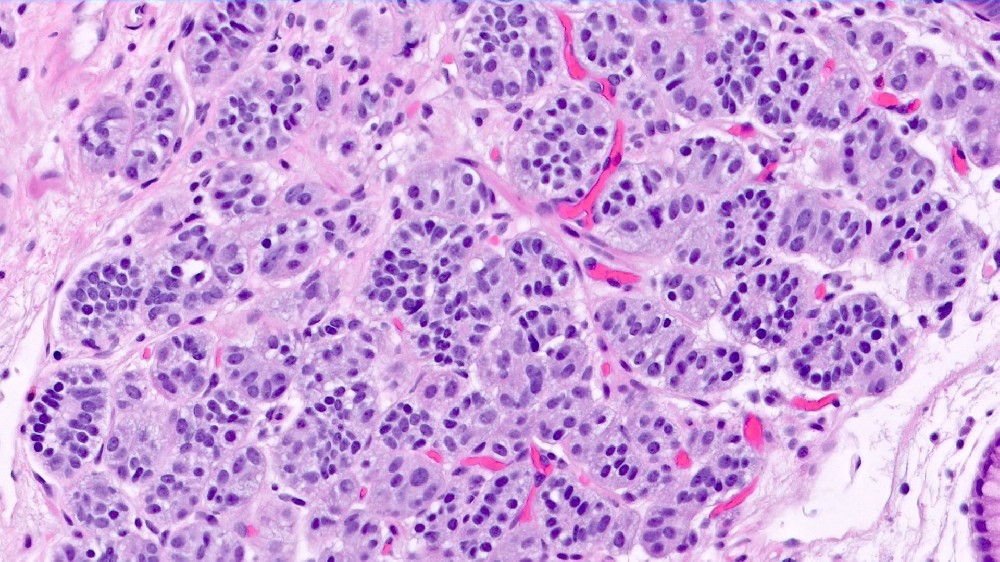

胃腸神經內分泌腫瘤 (Carcinoid Tumor) 是一種獨特的癌症,源自胃腸道 (GI) 內的神經內分泌細胞。這些重要的細胞會協調荷爾蒙的分泌,影響身體的多種功能,如消化和新陳代謝。與傳統癌症不同的是,這些腫瘤通常生長緩慢,但卻過度依賴葡萄糖代謝,並顯著表現出沃伯格效應 (Warburg effect),癌細胞消耗葡萄糖的速度比健康細胞快約 200 倍。瞭解胃腸道神經內分泌腫瘤 (Carcinoid Tumor),可讓患者和家屬以樂觀和清晰的態度控制病情。

胃腸神經內分泌腫瘤 (Carcinoid Tumors) 的代謝特徵是非常依賴有氧糖酵解,也就是一般所說的沃伯格效應。即使有足夠的氧氣,癌細胞仍主要將葡萄糖轉換成乳酸。這種新陳代謝的轉換使腫瘤細胞能夠維持快速生長,形成了尖端新陳代謝腫瘤學治療方法所利用的漏洞,例如李國華博士和劉國龍教授所開創的治療方法。

此外,神經內分泌癌細胞經常顯示谷氨酰胺依賴性,廣泛使用谷氨酰胺來合成核苷酸和製造能量。事實上,這些腫瘤中約有 50% 依賴穀胺通路,為新陳代謝靶向療法提供了治療機會。